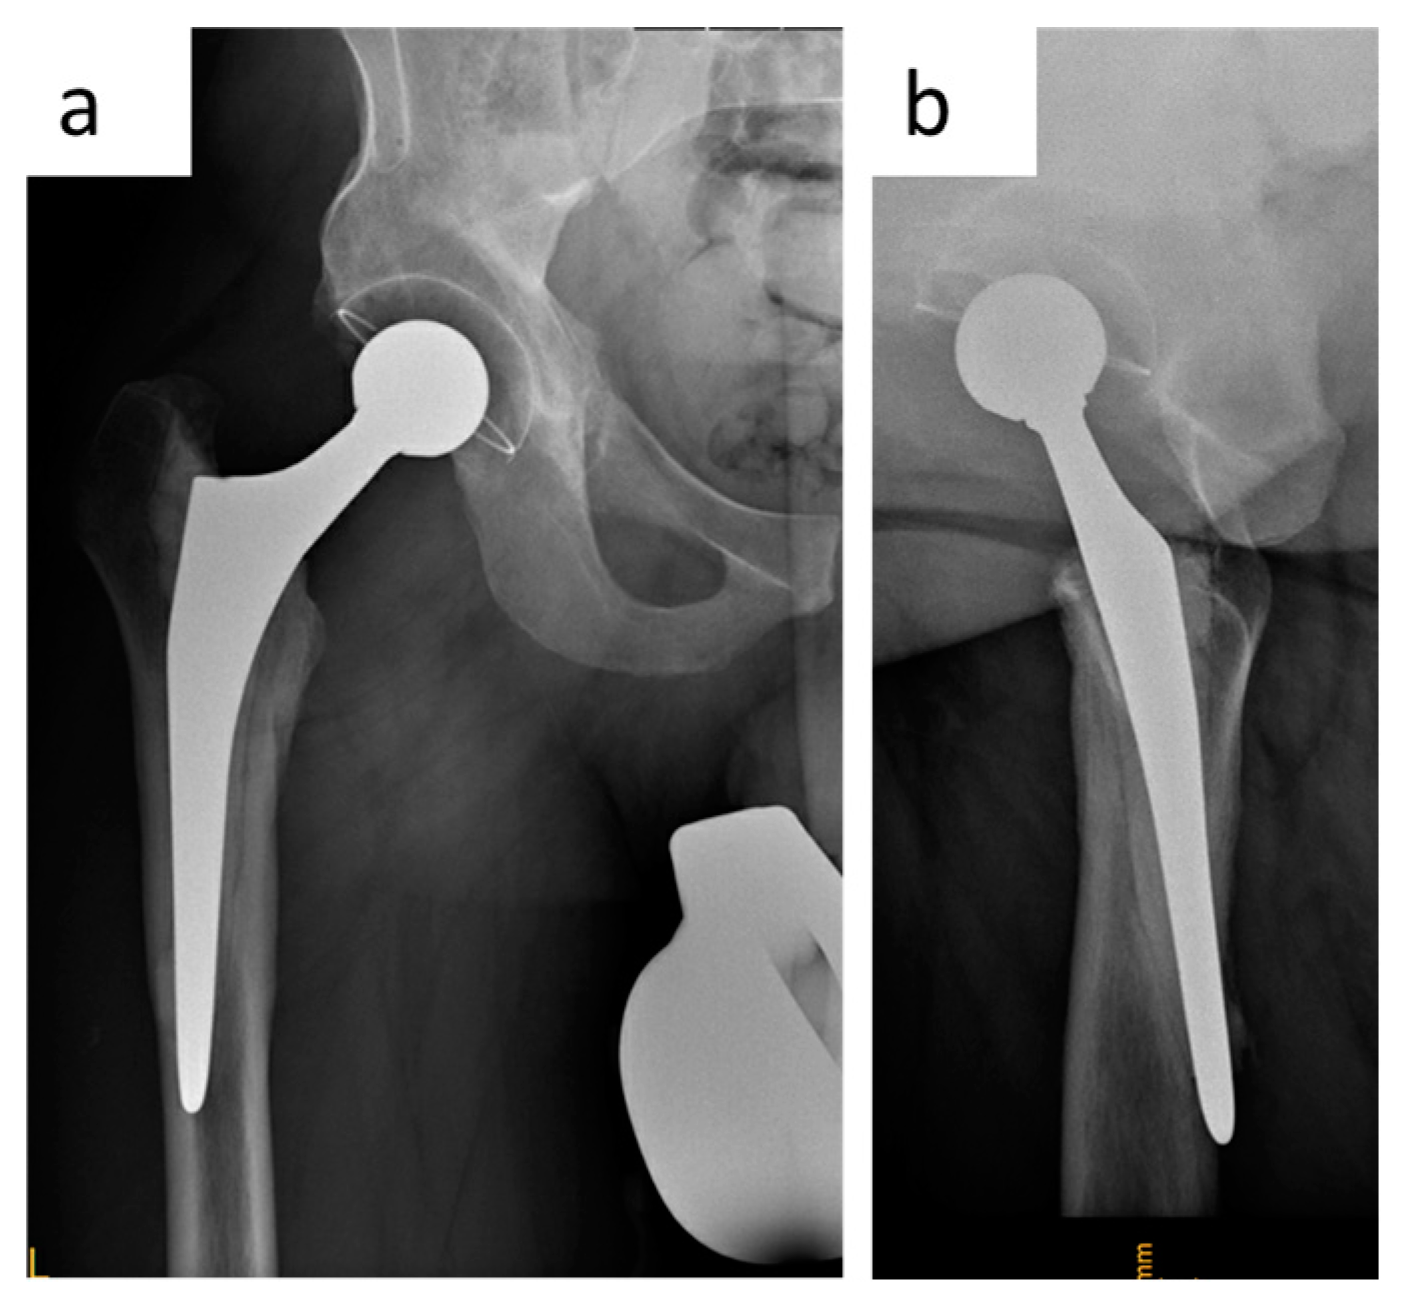

2.3.3. Clinical Case